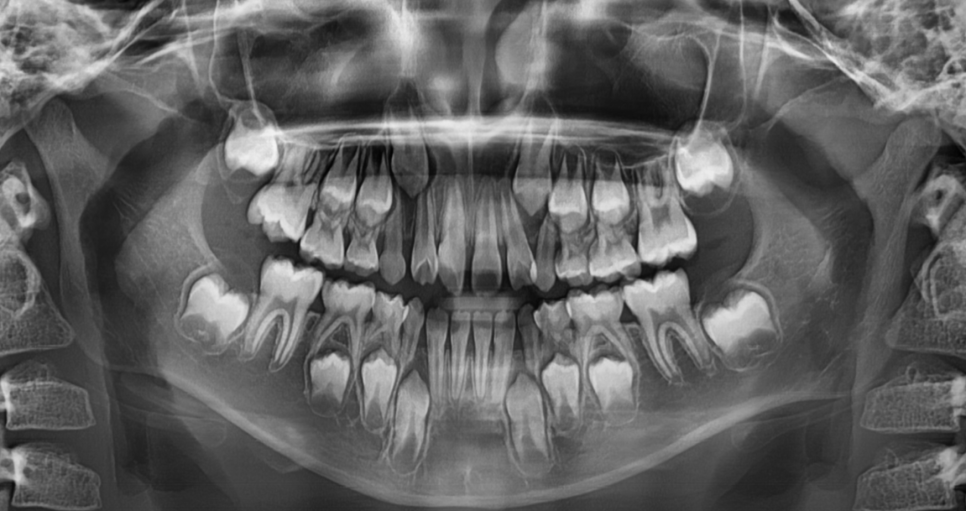

초등학교 1학년 아이의 치아입니다.

어린이 덧니로 인해

걱정이 되는 마음에 방문해주셨습니다.

어떤 아이들은 턱뼈 성장을 이용해야하기 때문에

영구치와 유치가 섞여있을 때 진행하고

어떤 아이들은 영구치 맹출이 끝난 후에 시작합니다.